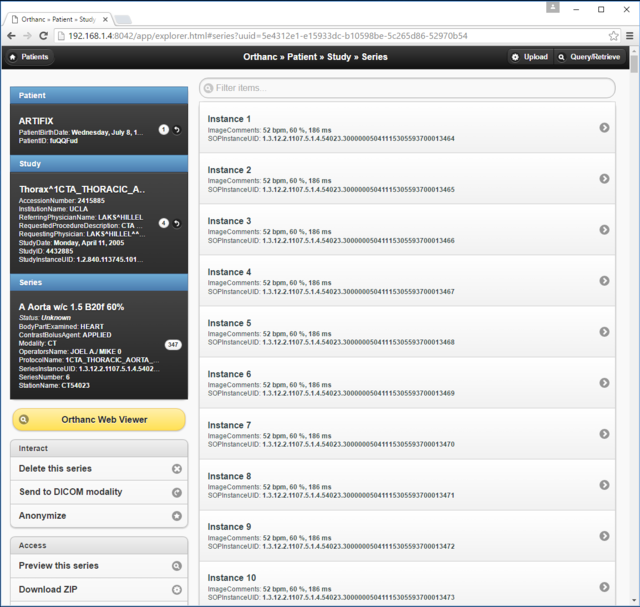

3. Orthanc DICOM server for medical imaging

- 1 x Orthanc PACS Server, installed on Ubuntu 16

- 1 x OrthancPi PACS Server, installed on Raspbian

- PACS: Picture Archiving and Communication System

- PACS (Picture Archiving and Communication System):

- Wikipedia page: https://en.wikipedia.org/wiki/Picture_archiving_and_communication_system

- DICOM (Digital Imaging and Communications in Medicine):

- Wikipedia page: https://en.wikipedia.org/wiki/DICOM

- Orthanc DICOM server: http://www.orthanc-server.com/